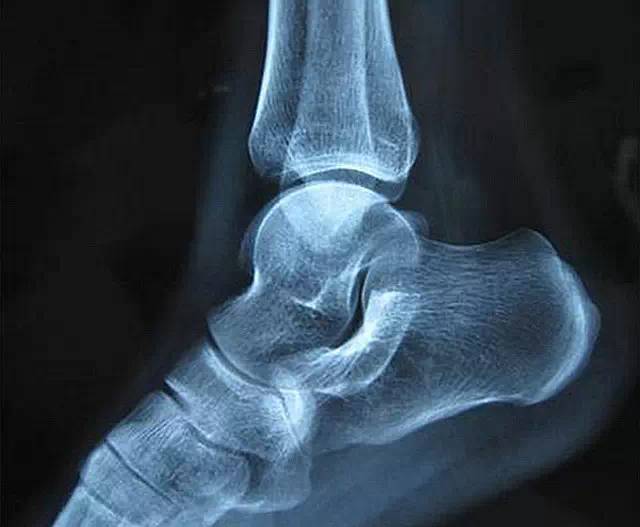

对于膝关节损伤,建议采用固定整个大小腿、并能够调整膝关节弯曲角度的支具,它的优点是固定牢靠,同时拆卸容易,而且在后期可以根据康复的进度调整角度。固定的时间一般是4-6周,时间太短,组织还没有完全修复;而时间太长则容易导致关节粘连,影响长期的关节功能。

除了固定的时间要严格遵守,还需要注意的是,受伤的一侧肢体尽量不要负重,也就是让它悬空,减少关节的微动,促进组织愈合。尤其是在半月板损伤的情况下,早期就利用支具步行不利于它的愈合。